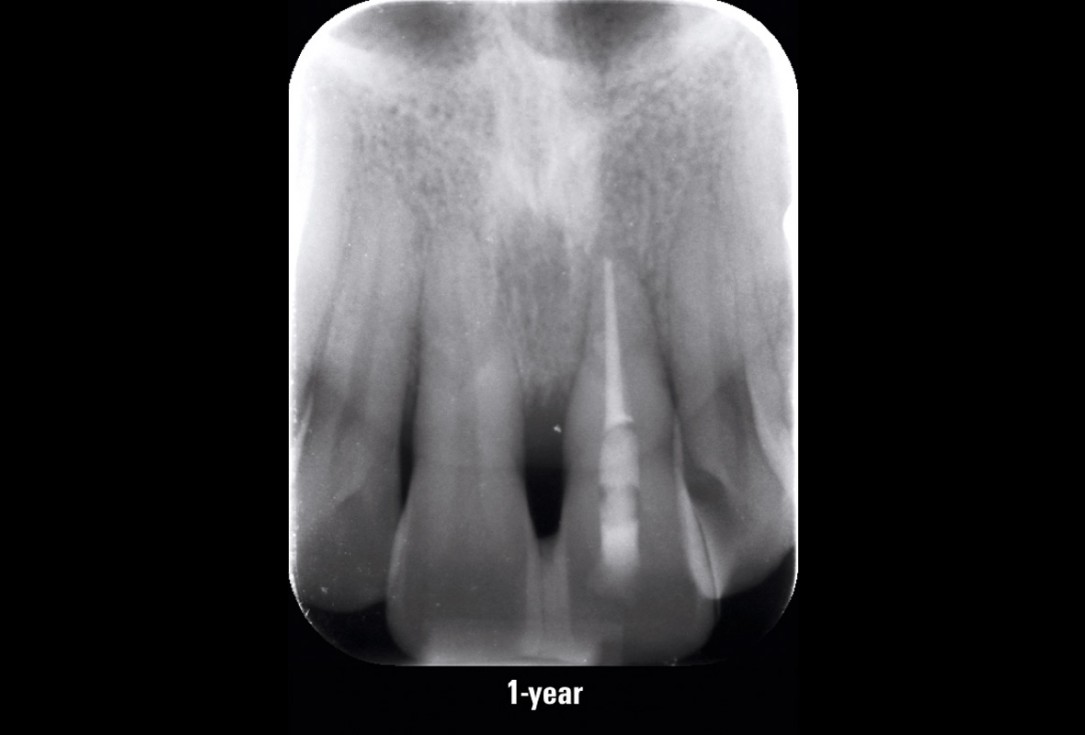

11/11 - Control x-ray at 1-year follow-upEntire papilla preservation technique (EPP) for the regenerative treatment of a severely compromised central incisor - Dr. S. Aslan